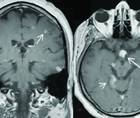

SOM fits well in the case of Ms V and is characterized by episodes of sudden-onset, rhythmic contractions of the superior oblique muscle of 1 eye leading to torsional eye movement, monocular oscillopsia, and vertical diplopia, especially on downward movement.7 Visual loss, dyschromatopsia, headaches, photophobia, periorbital swelling, and redness of the ocular surface do not occur. SOM is typically idiopathic, presumed to result from neurogenic hyperexcitability of the superior oblique muscle. In rare cases, SOM may be the result of trochlear nerve compromise at the nerve root exit zone by a superior cerebellar artery, cyst, brain tumor, or dural arteriovenous fistula (AVF).